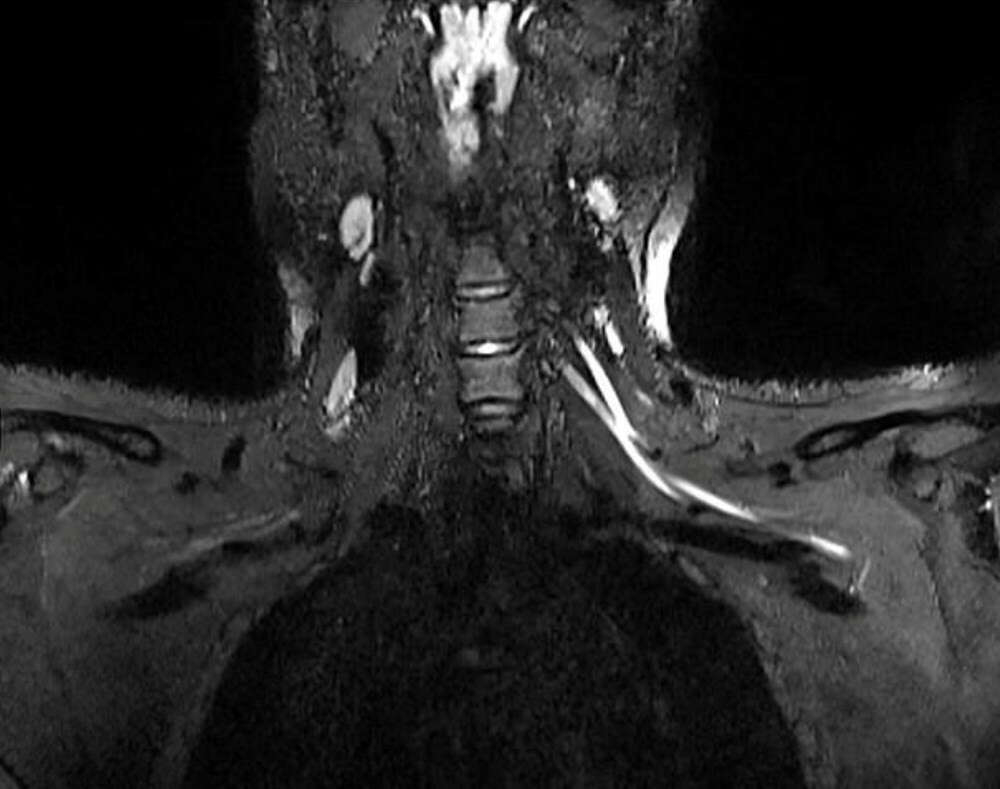

Bilim insanları uzun süreli yeni tip corona virüs (Covid-19) hastalarında görülen yorgunluk ve ağrının sebebini ilk kez ortaya koydu. ABD'de yer alan Northwestern Üniversitesi'nden araştırmacılar MRI ve ultrason tekniklerini birleştirerek, geleneksel yöntemlerle tespit edilemeyen Covid-19'un sinir sisteminde yarattığı hasarı kanıtladı. Geliştirilen yeni teknolojinin doktorlara, hastaları için uygun tedavi yöntemini belirlemesini sağlayarak hayat kurtarabileceği belirtildi.